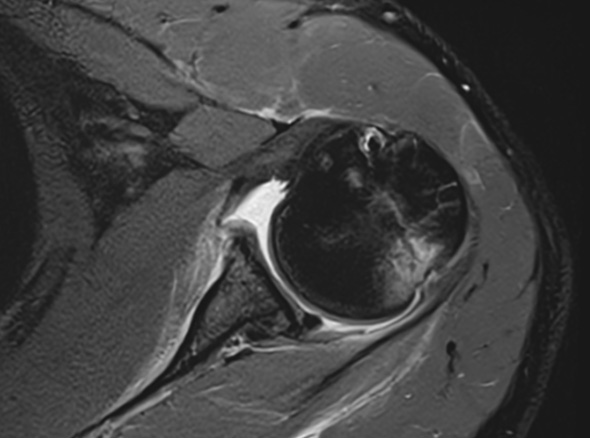

어깨가 가볍게 빠지는 증상, 어깨와 팔꿈치 사이에 있는

상완골이 어깨뼈에서 빠져나오는 증상을 어깨 탈구라고 합니다.

상완골두의 울타리 역할을 하는

관절와순 순상이 동반되는 경우도 있습니다.

재발성 탈구(2회 이상)인 경우

첫 탈구이나 관절와순이 전위되어 있어

재탈구 가능성이 높은 경우